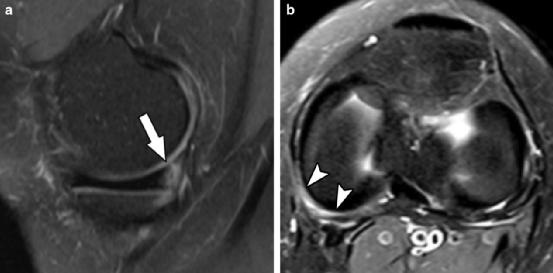

1型半月板斜坡损伤磁共振成像病例。矢状面(a)和轴向T2加权脂肪抑制图像显示半月板关节囊撕裂(箭头)伴胫骨挫伤,半月板关节囊连接处水肿(箭头)